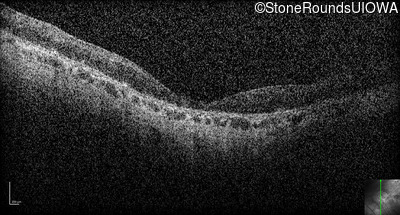

Optical Coherence Tomography - Right - Hand Motion 1' sc

Exemplar / OCT Stack

Optical Coherence Tomography - Left - Hand Motion 6" sc